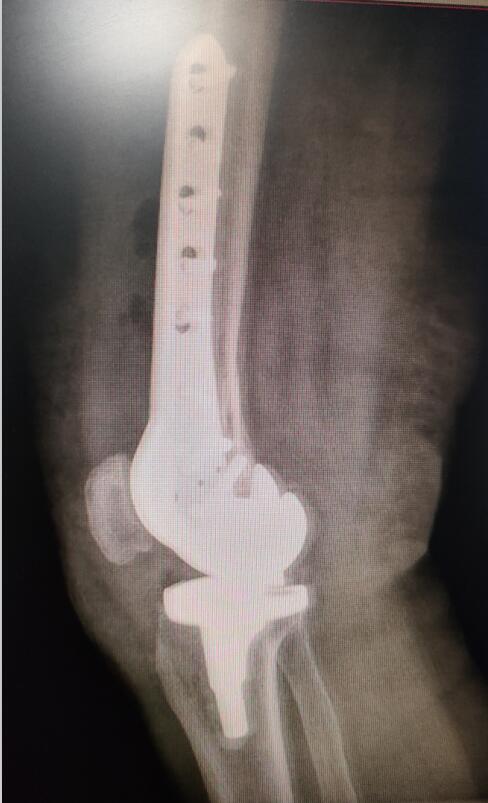

手术前照片

手术后照片